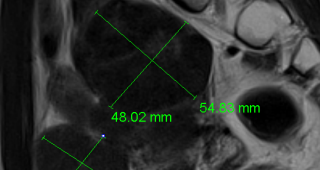

자궁근종 비수술 하이푸 치료 후 분만사례입니다. 자궁근종 하이푸 치료는 자궁근종 부위만 선택적으로 치료하는 시술로 자궁근종 전체적으로 시술하였습니다. 8cm 액화변성 자궁근종 하이푸 치료 시간은 57분이...